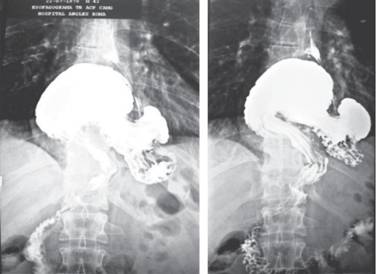

En todos los pacientes se realizó en el postoperatorio un examen radiológico esofágico estándar a los tres y 12 meses postquirúrgicos. Con base en lo mencionado por la literatura, definimos como “hernia hiatal paraesofágica gigante” a la migración al tórax de más un tercio del estómago con o sin otros órganos (Figura 1).10,11